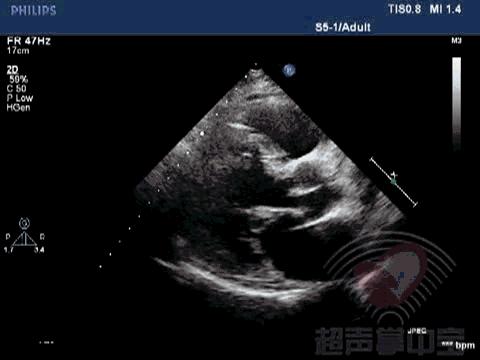

经典病例▏二尖瓣囊肿中竟然全是血液? 动态图3:左室长轴切面观察该囊状物质软,有形变,随二尖瓣运动而摆动

经典病例▏二尖瓣囊肿中竟然全是血液? 动态图4:心尖左室长轴切面观察该囊状物质软,有形变,随二尖瓣运动而摆动